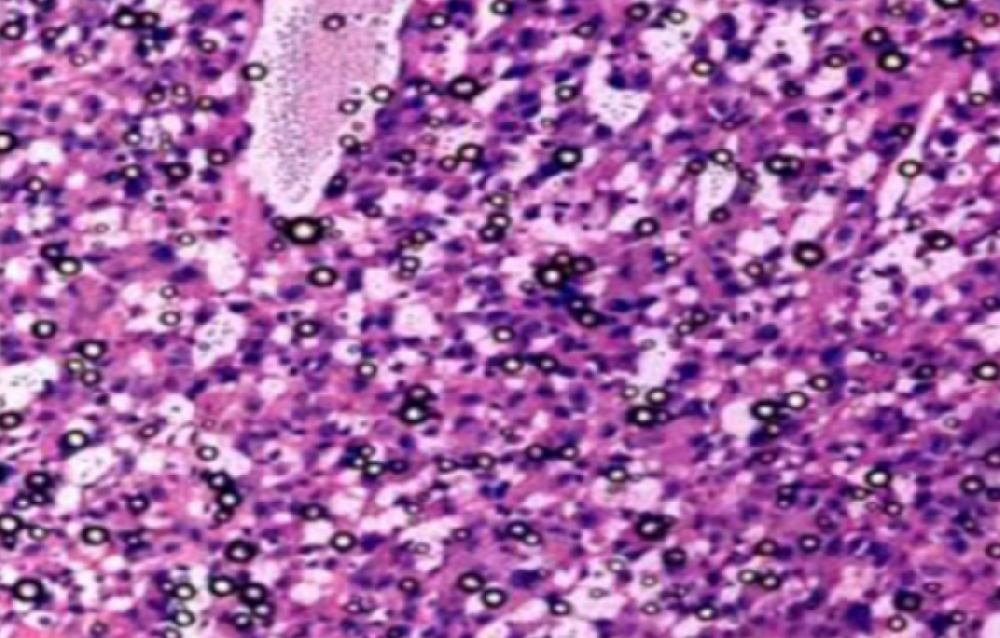

①常规HE染色,切片厚度需要根据不同组织类型而定。

②光镜下首先区分有否特异性病变及范围,然后由脏器一端向另一端进行整体观察和描述。

③观察小动物脏器有否肿大、增生,用10倍镜由一端开始计数该脏器包含的10倍镜镜头视野数,或计数整个切片中功能单位数。如脾生发中心、胸腺小叶、肝小叶、肾小球及整个切片中病变灶数量。

④大动物脏器疑有肿大、增生时,用40倍镜头计数每一视野中的细胞或功能单位数。心肌、骨骼肌在与长轴平行的切面上计数每一视野直径中的肌纤维数、肝小叶中肝细胞索数(数40倍镜视野的一半)。根据需要计数10~20个40倍镜视野。